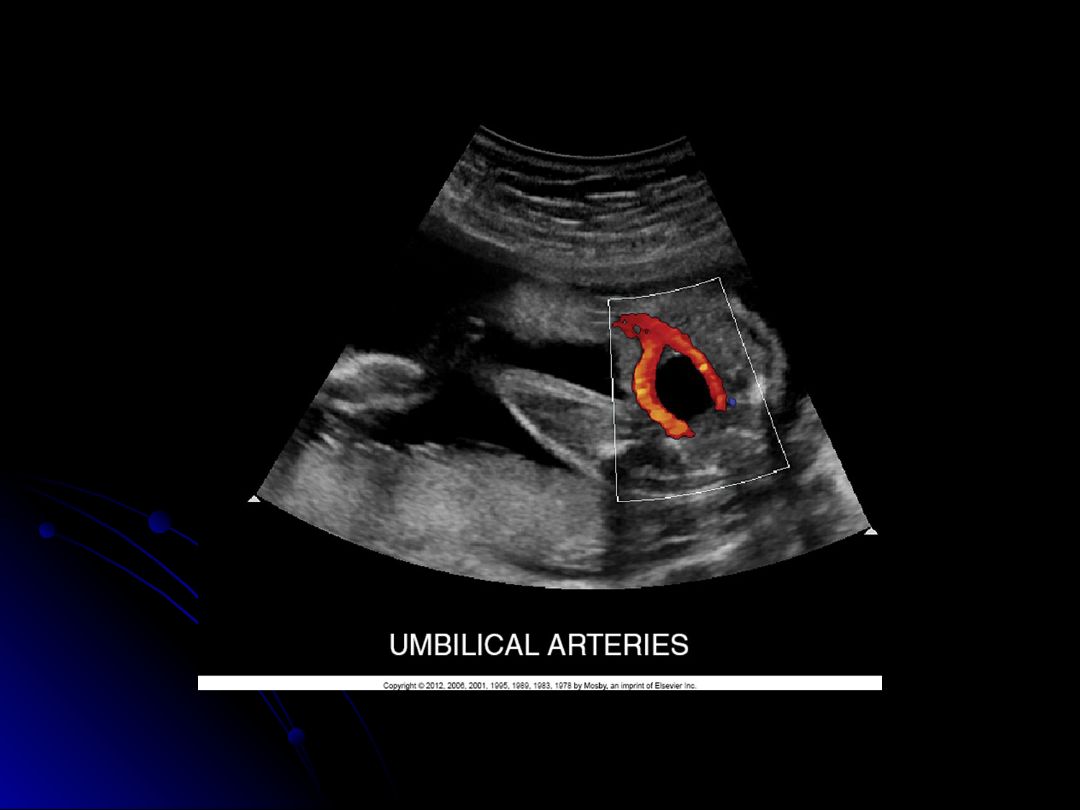

Based on the sonographic appearance, what are two key features to assess in the umbilical cord during gestation?

Cord twist and number of umbilical arteries

In the ultrasound image, which vessel is identified as the largest within the umbilical cord?